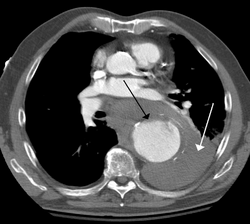

Contrast enhanced CT of a ruptured large (7 cm) thoracic aneurysm, with black arrow indicating the aorta, and white arrow blood in the thorax

The principal causes of death due to thoracic aneurysmal disease are dissection and rupture. Once rupture occurs, the mortality rate is 50–80%. Most deaths in patients with Marfan syndrome are the result of aortic disease.[citation needed]